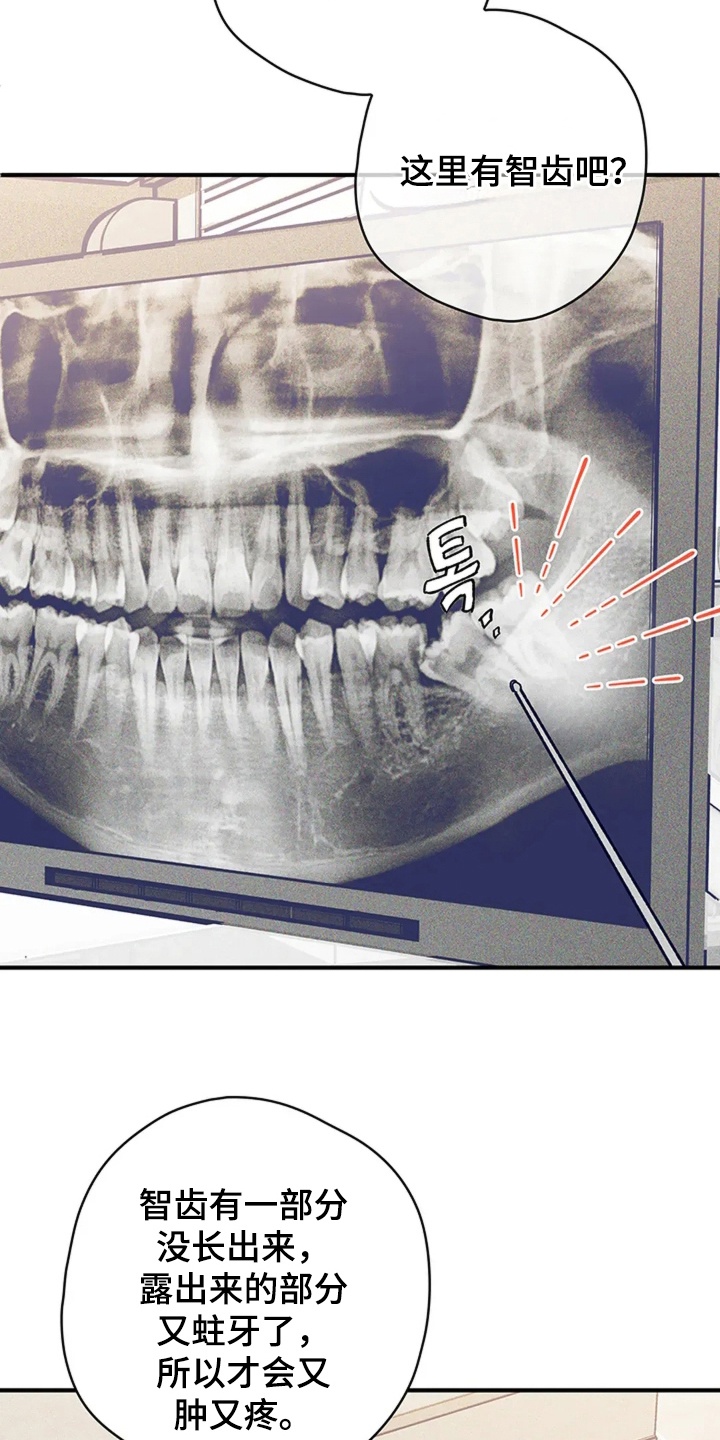

第1章:牙疼真要命